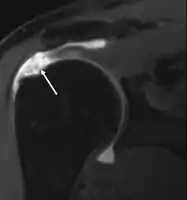

MRI

Magnetic resonance imaging (MRI) and ultrasound[42] are comparable in efficacy and helpful in diagnosis although both have a false positive rate of 15–20%.[43] MRI can reliably detect most full-thickness tears although very small pinpoint tears may be missed. In such situations, an MRI combined with an injection of contrast material, an MR-arthrogram, may help to confirm the diagnosis. It should be realized that a normal MRI cannot fully rule out a small tear (a false negative) while partial-thickness tears are not as reliably detected.[44] While MRI is sensitive in identifying tendon degeneration (tendinopathy), it may not reliably distinguish between a degenerative tendon and a partially torn tendon. Again, magnetic resonance arthrography can improve the differentiation.[44] An overall sensitivity of 91% (9% false negative rate) has been reported indicating that magnetic resonance arthrography is reliable in the detection of partial-thickness rotator cuff tears.[44] However, its routine use is not advised, since it involves entering the joint with a needle with potential risk of infection. Consequently, the test is reserved for cases in which the diagnosis remains unclear.